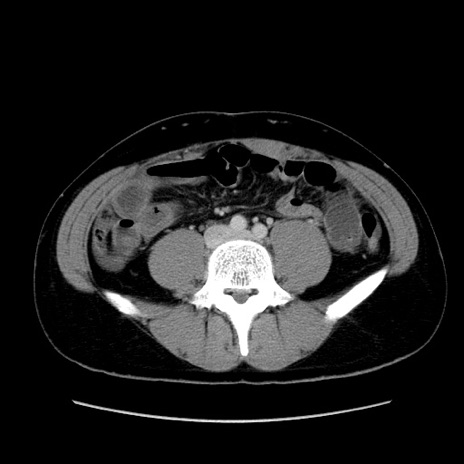

症例36(横断像)

【症例】20歳代 男性

【主訴】心窩部痛

【現病歴】今朝より上腹部痛あり。一旦軽快していたが再度出現したため救急要請。昨日夕に白身の魚を含む刺身を食べた。

【身体所見】BP 136/89mmHg、HR 74/min、BT 37.0℃、腹部:膨満、軟、心窩部に圧痛あり。反跳痛なし、筋性防御なし、腸雑音やや亢進あり。

【データ】WBC 17700、CRP 0.48